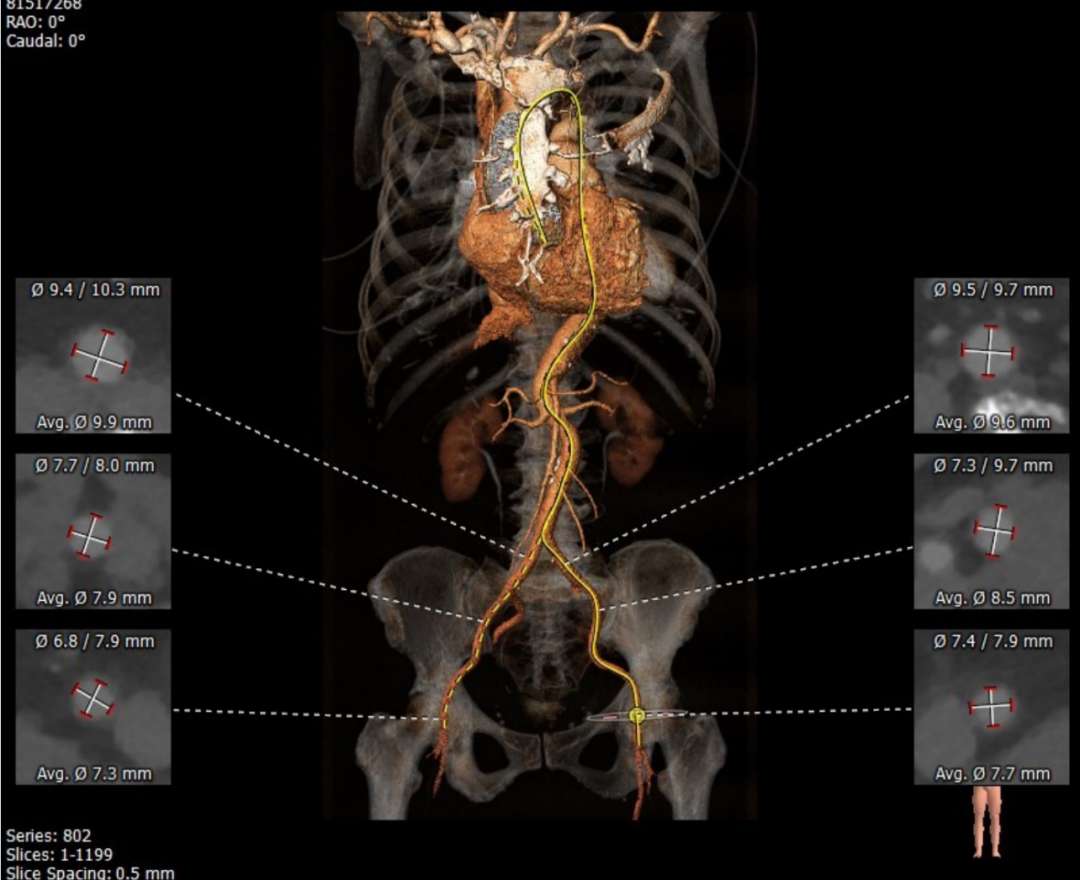

主动脉瓣瓣环周长71.4mm,周长径22.7mm,LVOT 25.2mm,STJ 34.6mm。CT数据分析显示该患者为Type1型二叶瓣,瓣叶重度钙化且增厚,钙化集中分布于左无冠瓣交界处,HU850:579mm²。

左冠开口高度14.5mm,右冠开口高度12.1mm,双侧冠脉开口未见明显附壁钙化,结合瓦氏窦宽度和瓣叶长度综合判断冠脉阻挡风险低。

升主动脉扩张,平均周长径48.3mm,主动脉瓣环与水平面夹角71°,主动脉弓角与弓距可。

双侧血管内径可,无明显迂曲,符合血管入路条件。

主动脉瓣瓣环周长85.4mm,周长径27.2mm,LVOT 28.1mm,STJ 29.4mm。CT数据分析显示该患者为Type1型二叶瓣,瓣叶重度钙化且增厚,主要分布于无冠瓣叶,左冠窦有团状钙化并延伸至左室流出道,HU850:957mm²。

左冠开口高度13.0mm,右冠开口高度16.5mm,双侧冠脉开口未见明显附壁钙化,结合瓦氏窦宽度和瓣叶长度综合判断冠脉阻挡风险较低。

升主内径36.0mm,主动脉瓣环与水平面夹角39°,主动脉弓角与弓距可。

双侧血管内径可,无明显迂曲和附壁钙化,符合血管入路条件。